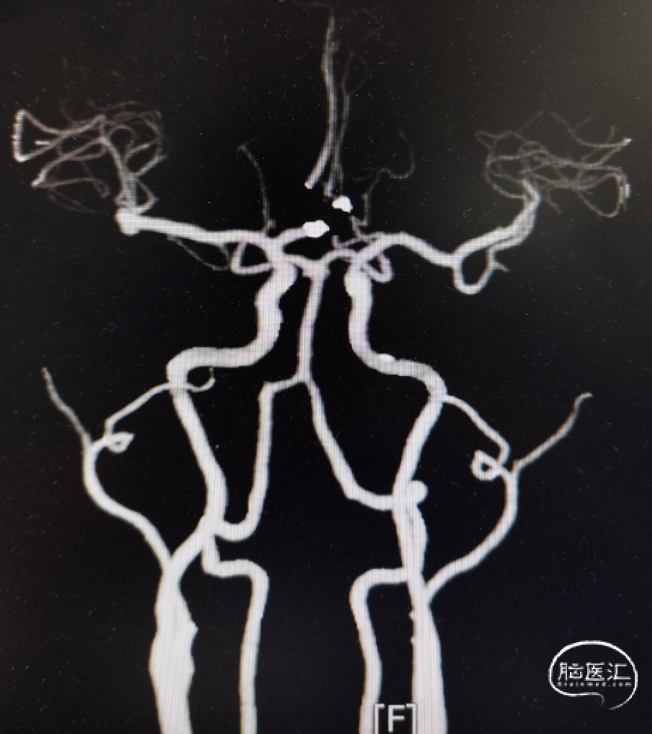

头颅CT显示:额叶蛛网膜下腔出血。

完善头颅CTA显示:前交通动脉瘤、左侧大脑中M1段末端动脉瘤。

DSA造影确认前交通动脉瘤、左侧大脑中M1段分叉部动脉瘤。

前交通动脉瘤5.94mm*4.12mm,瘤体呈分叶状。

患者右侧大脑前发育纤细;后循环血管无明显异常。